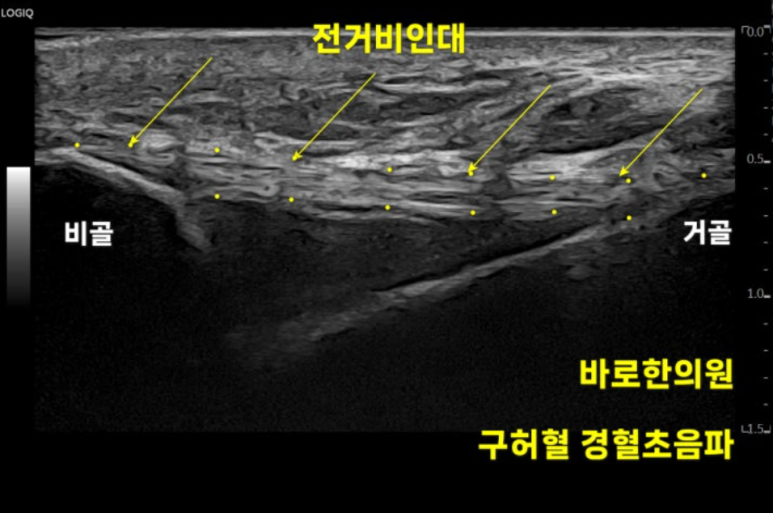

정상적으로

일자로 주행하는

밝은 인대 섬유가

비슷한 두께로 보여야 합니다.

하지만 우리 환자분

왼쪽 발목 구허혈은

전거비 인대가 완전파열되어

인대가 보이지 않고

관절도 까맣게 부어있습니다.